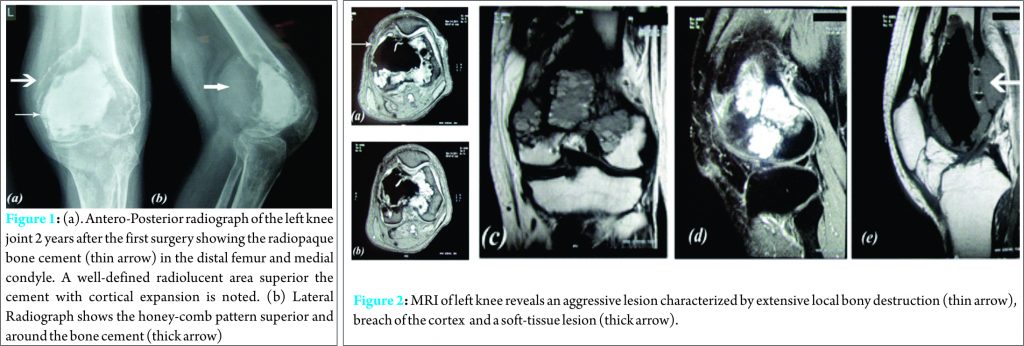

A 37-year-old male presented with complains of pain around the left knee joint. The patient had similar complains 2 years ago and was diagnosed with a GCT of the left distal femur for which he was treated with an intralesional curettage and Poly methylmetacrylate implantation. On examination, there was a swelling over the left knee, which was bony in consistency and was associated with painful and restricted movements of the knee joint. Radiographs of the left knee were obtained (Fig. 1) which indicated a recurrence of the GCT with the hallmark honeycomb appearance, ballooning and breach of the cortex posteriorly as well as a soft tissue mass, suggestive of an aggressive giant cell tumor. Magnetic Resonance Imaging (Fig. 2) revealed an area of hypointensity corresponding with the Cement and multiple loculated hyperintense lesions in the metaphysis of distal femur. Also noted was the breach of the cortex with extension of the mass into the adjacent soft tissue (Campanacci Grade 3 lesion).